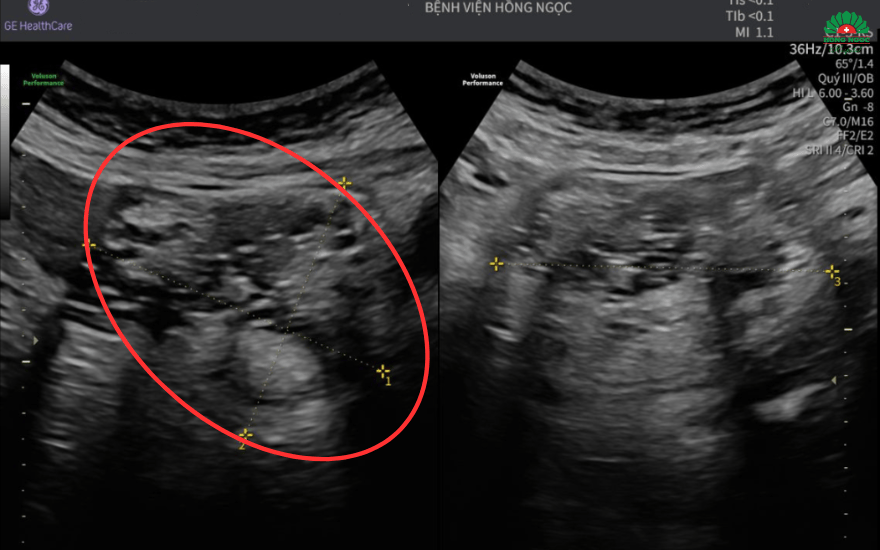

Tại đây, chị được chỉ định siêu âm và chụp MRI ổ bụng, kết quả cho thấy u buồng trứng kích thước hơn 7cm cùng hình ảnh mô đặc, mỡ, xương - gợi ý u quái trưởng thành. Để ngăn chặn biến chứng ảnh hưởng đến sức khỏe, các bác sĩ quyết định thực hiện phẫu thuật nội soi loại bỏ khối u cùng hai phần phụ.

Khối u buồng trứng kích thước hơn 7cm chèn ép các tạng xung quanh.